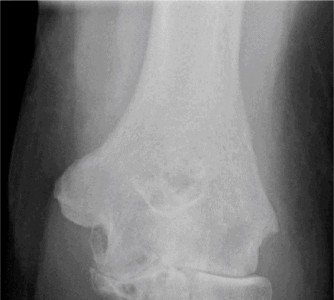

Clinical presentation typically involves progressive pain, stiffness, loss of motion (especially extension and flexion), mechanical symptoms like clicking or locking, and sometimes ulnar nerve irritation due to osteophyte encroachment. Diagnosis relies on a comprehensive history, physical examination, and radiographic evaluation demonstrating joint space narrowing, osteophytes, subchondral sclerosis, and possibly loose bodies.

- Standard Radiographs: AP, lateral, and oblique views are crucial for assessing joint space narrowing, osteophyte burden (anterior coronoid, posterior olecranon, radial head), subchondral sclerosis, and the presence of loose bodies. Weight-bearing views are not typically used for the elbow.

| Radiographic Changes | Early OA: mild joint space narrowing, minimal osteophyte formation, no loose bodies. | Moderate to severe OA: significant joint space narrowing, large osteophytes (anterior/posterior), subchondral sclerosis, loose bodies, gross articular incongruity, subchondral cysts. |